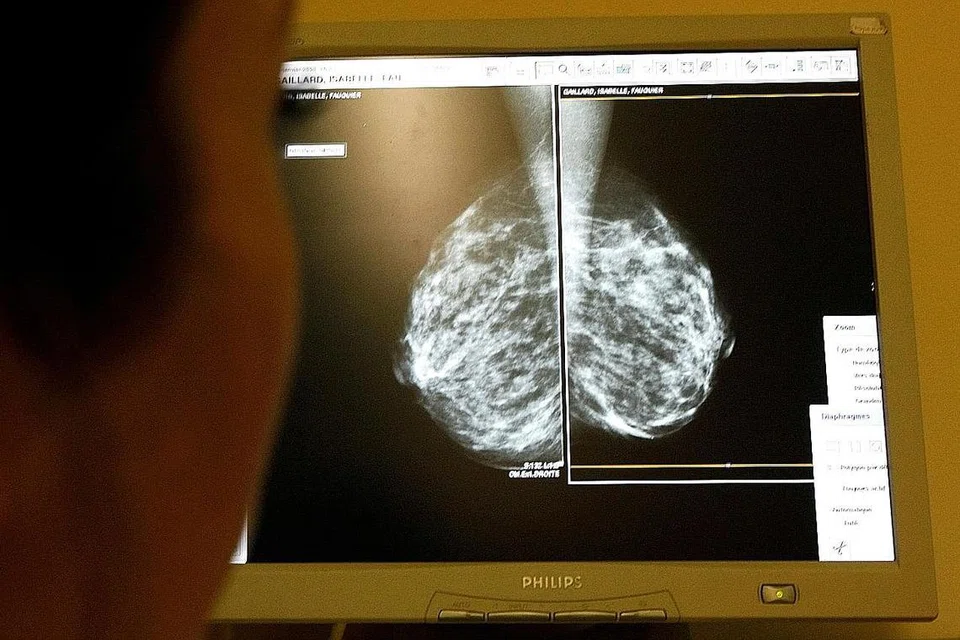

MAMOGRAFI adalah pemeriksaan paling mudah dan penting bagi barah buah dada.

Ia adalah X-ray dos rendah buah dada dan boleh mengesan penyakit barah bertahun-tahun lebih awal sebelum seorang wanita atau doktor mungkin dapat rasakan ketulan.

Barah buah dada pada tahap awal mungkin tidak menunjukkan sebarang gejala, tetapi menjelma sebagai ketumpatan abnormal atau mendapan kalsium dalam payudara yang dikesan dalam mamogram.

Matlamat pemeriksaan mamogram adalah untuk mengesan barah pada peringkat awal, apabila tumor masih kecil.